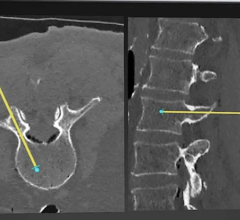

Ziehm’s Object Detected Dose Control feature for the Vision line of C-arms purportedly improves image quality with a low dose while also making the system easier to handle. The new real-time image control covers the whole field of view and provides independent object positioning within the field.

The tool allows real-time motion detection, which adjusts the noise reduction level whenever there are moving objects. The system also reduces the pulse frequency in the case of non-moving objects. The new tool also features automatic metal correction to reduce the blooming effect, to produce optimal image quality even when there is metal in the image.